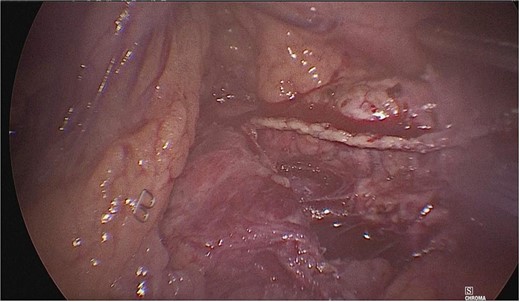

Once the above procedure was completed, it was dissected along the neck of the pancreas to identify the superior mesenteric vein and splenic vein. An incision was made along the superior border of the pancreas, to the left of the gastroduodenal artery and inferior to the hepatic artery. A plane was created between the portal vein and neck of the pancreas by blunt dissection from the inferior to the superior direction with a blunt-tipped laparoscopic dissector (Fig. 2).

A plane was created between the portal vein and the neck of the pancreas by blunt dissection.